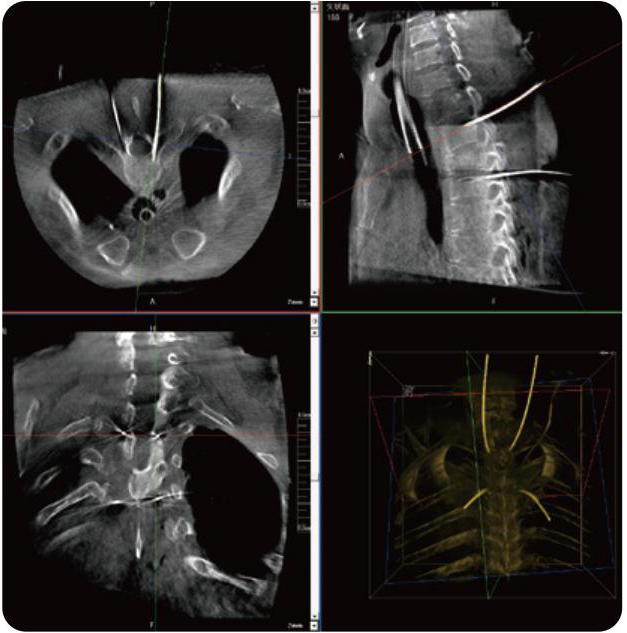

PL300B可應用于多節段脊柱外科手術,輔助醫生定位病灶部位,為脊柱外科手術(經皮椎體成形術、椎弓根螺釘內固定術等術式)提供術前手術流程規劃、入釘位置、角度可視化引導,模擬仿真入釘輔助。

PL300B搭配普愛醫療自主研發生產的平板3D C形臂,借助一體化自適應配準( 軌跡配準)技術,通過追蹤C形臂三維采集軌跡,自動完成圖像坐標建立和系統坐標配準。配準精度更高,操作步驟少,系統運作效率高。